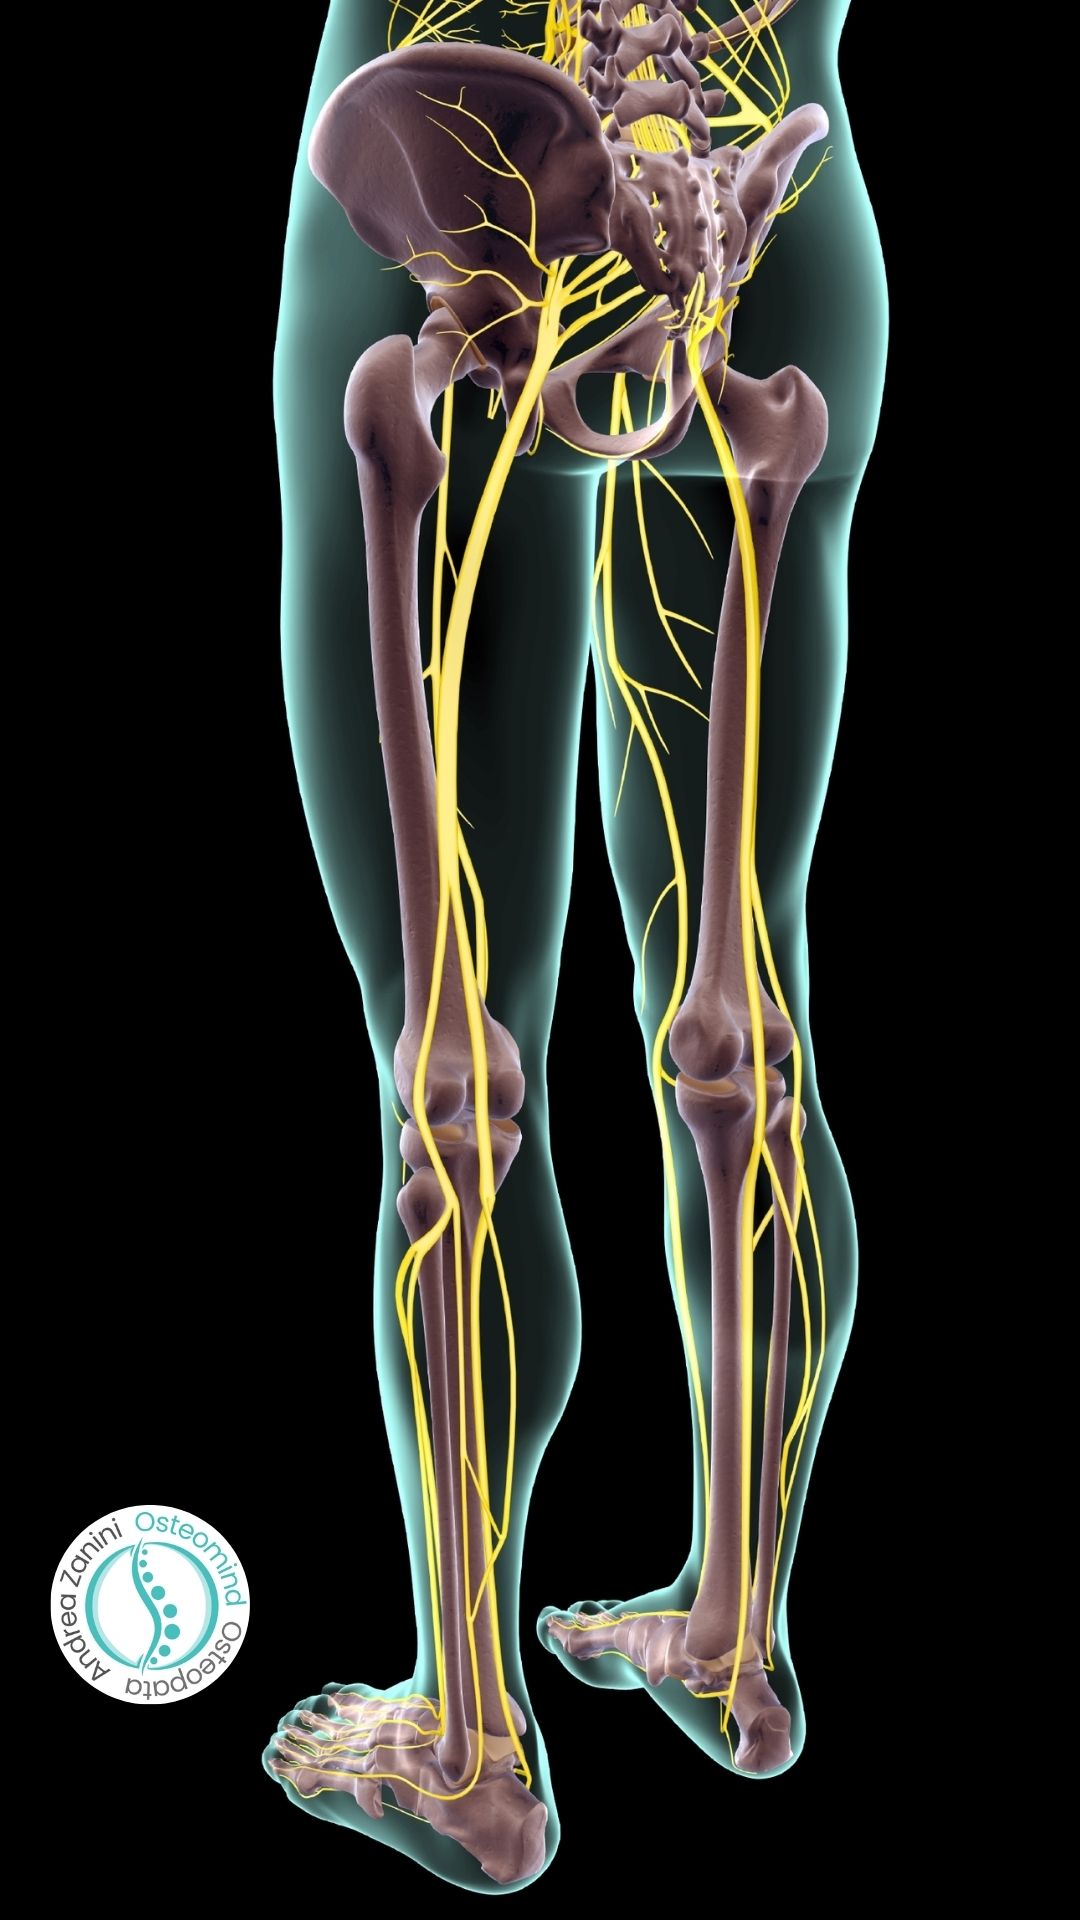

La sciatalgia, comunemente chiamata “sciatica”, è uno dei disturbi più frequenti a Milano tra chi trascorre molte ore seduto in ufficio, guida quotidianamente nel traffico cittadino o svolge lavori che comportano sforzi fisici ripetuti. Il dolore, che può essere veramente invalidante, si manifesta lungo il decorso del nervo sciatico, dalla zona lombare scende sul gluteo, sulla coscia e talvolta fino al piede.

La sciatica (o sciatalgia) è un dolore che si diffonde lungo il percorso del nervo sciatico, il nervo più lungo del corpo umano. Origina dalla zona lombare e scende lungo il gluteo, la parte posteriore della coscia, fino ad arrivare al piede.

Il sintomo principale della Sciatalgia è un dolore che segue il percorso del nervo sciatico. A differenza di un dolore muscolare localizzato, questo tende a irradiarsi lungo l’arto inferiore.

Il dolore parte dalla zona bassa della schiena o dal gluteo e scende posteriormente e lateralmente lungo la coscia, fino ad arrivare alla porzione esterna del piede. Peggiora a seguito di sforzi fisici, dopo tosse e starnuti o dopo essere stati seduti per troppo tempo. - Bruciore, pugnalata e formicolio